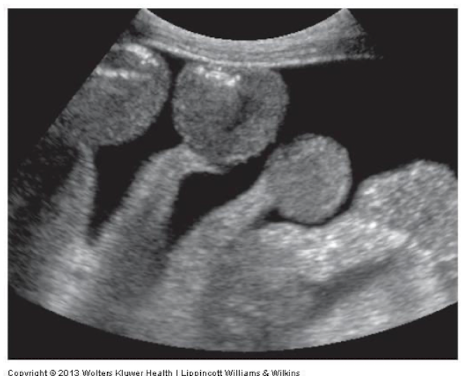

This is an image of:

Simple ascities with small bowel floating freely in the ocean